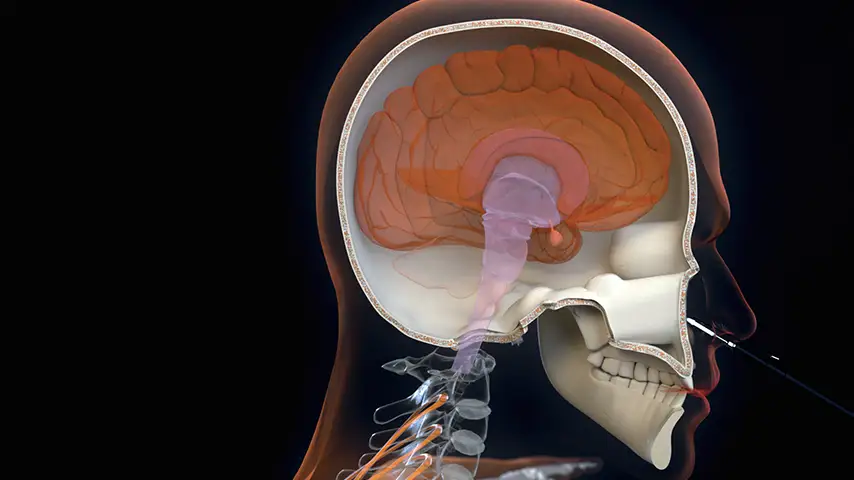

Endoscopic transsphenoidal approach

Clinical Applications of PIEZOSURGERY® technology

in Pediatric Neurosurgery